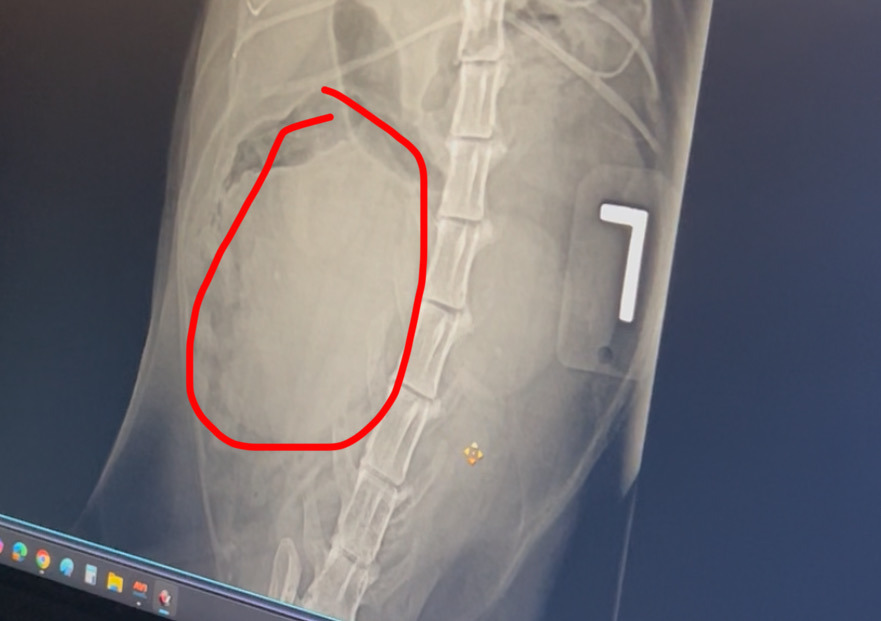

Recently, Luna was found to have a large tumor that requires surgery. Watching her change has been heartbreaking. She went from being her usual cuddly, sweet self to withdrawing and isolating. Luna has always been so expressive, known for using her little voice to “talk” to me throughout the day, but now she barely makes a sound.